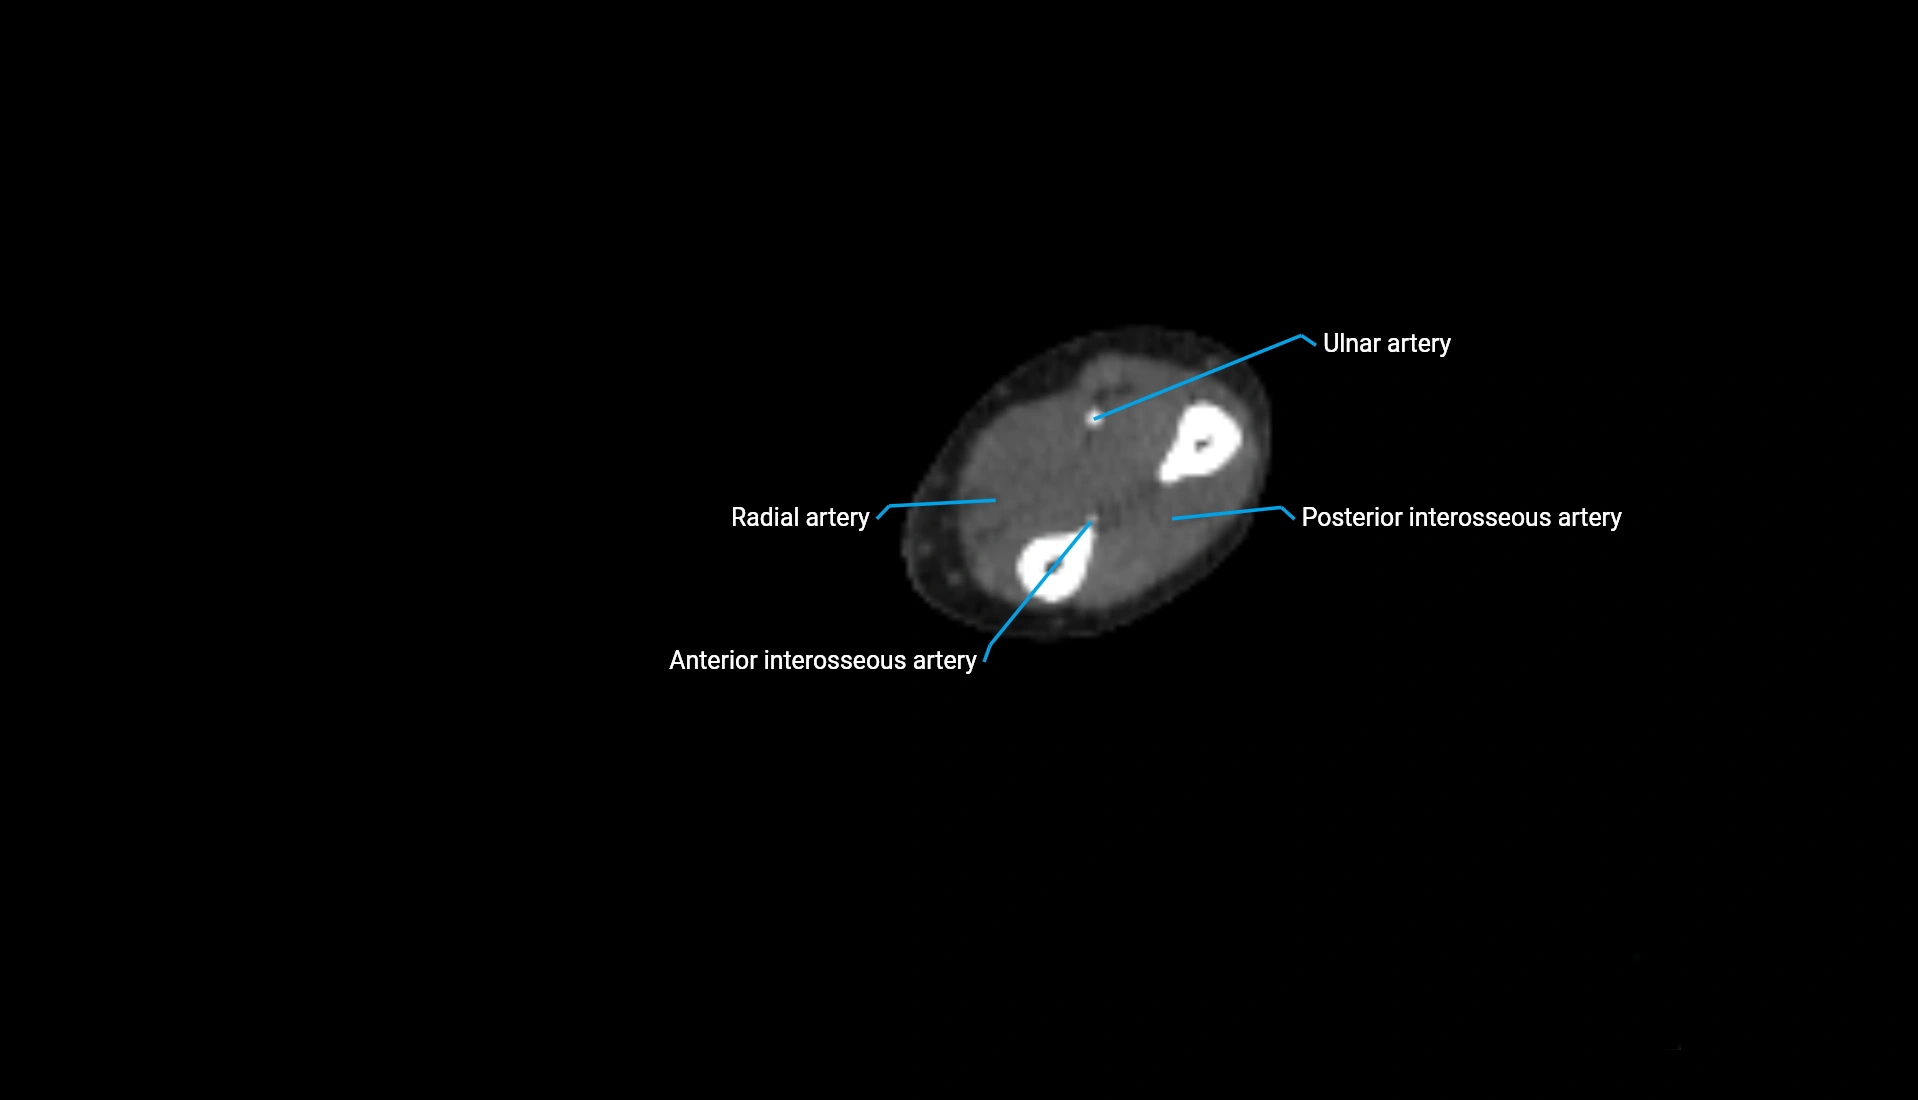

CT Appearance

Non-Contrast CT:

• Cortex: High-density, sharply defined

• Subchondral bone: Dense cancellous matrix

• Articular surface: Smooth concave contour articulating with the capitellum

• Excellent for evaluating bone integrity, alignment, and subtle fractures

Post-Contrast CT:

• Bone: No enhancement

• Joint capsule and synovium: Mild enhancement outlining the joint

• Improves contrast between soft tissues and bony margins

• Useful in detecting subtle joint abnormalities or postoperative changes